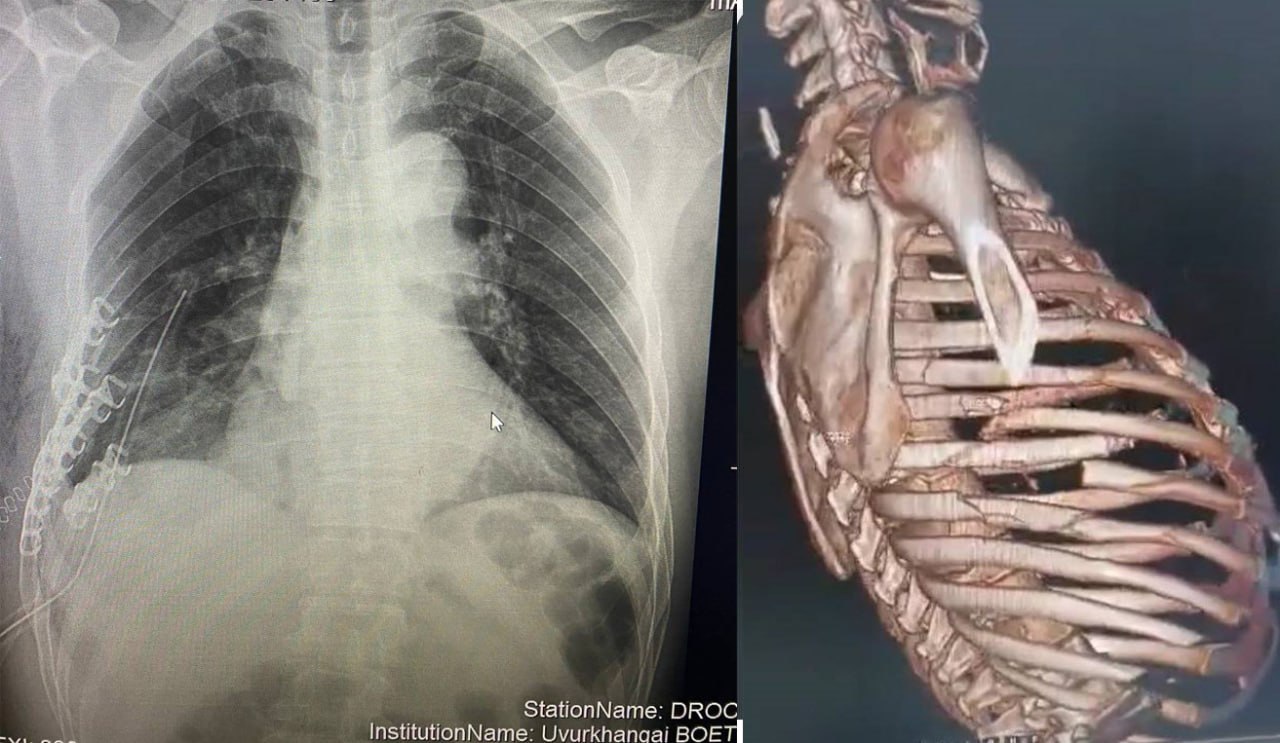

| АЛСЫН ДУУДЛАГЫН БАГ ӨВӨРХАНГАЙ АЙМАГТ ХАВСАРСАН ХҮНД ГЭМТЭЛТЭЙ ӨВЧТӨНД ЯАРАЛТАЙ МЭС ЗАСАЛ ХИЙЛЭЭ |